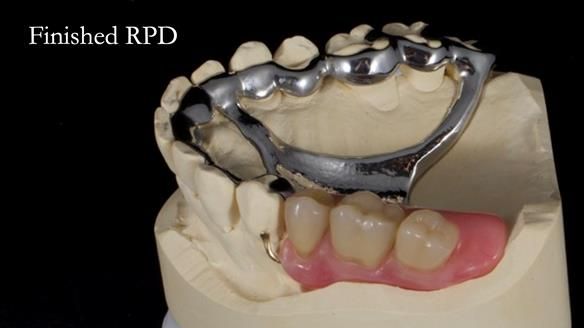

Welcome to Newsletter 64. I'll walk you through the process of providing a Mk 2 metal-based partial denture (RPD), for Ian a retired Veterinary Surgeon aged 78. The RPD was made at an increased vertical dimension and acted as an occlusal stabilisation splint - reducing the wear and bite force on the remaining natural teeth.